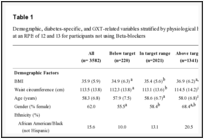

A 28-year-old man with no medical problems was referred to the Department of Periodontology showing purulent exudate formation and tooth mobility with deep periodontal destruction involving mesial, mid-buccal and slightly distal portion of the root in combination with 4 mm buccal recession in tooth #23 (FDA classification) (Figure 1). Clinical probing depths and other baseline clinical variables were shown in Table 1. Other periodontal symptoms were bleeding on probing, pus formation, slight edema and redness with mild tactile and air blast sensitivity. As possible adjunctive etiologic factors, the tooth root was slightly inclined in labial direction and a premature contact was present. Radiographically, a significant radiolucency extending to the middle third of the mesial root surface was observed with a concomitant widening of the periodontal ligament space and loss of lamina dura in the surrounding alveolar bone (Figure 2).

Following both surgeries, chlorhexidine digluconate and non-steroidal anti-inflammatory drugs were prescribed. The sutures were removed at 10 days. All periodontal clinical measurements and radiographic examination were repeated 6 and 12 months after second surgery, by the same clinician. Compared to baseline, significant improvements were detected at all periodontal clinical measurements (Table 1). Probing depths were reduced and gingival recession was completely covered. In the clinical examination, the gingiva was healthy with its pink and firm view and no bleeding on probing was detected at 12 months postsurgical examination. There was good color blending of the treated area with the adjacent soft tissue (Figure 8). Due to two-step surgical procedure, surgical scar was present and a minor recession (approximately 0.5 mm) occurred in adjacent lateral and premolar teeth. However, no root hypersensitivity was detected. Radiographically, view of complete defect fill was maintained adjacent to the mesial root surface of the treated tooth and no root resorption or other complications were present (Figure 9). The patient was satisfied with outcomes of the treatment.

Table 1:

Periodontal clinical measurements.

PI=plaque index; GI=gingival index; PD=probing depth; AL=attachment level; KT=keratinized tissue; GR=gingival recession; mes=mesial; mid=mid-buccal; dis=distal; Mob=mobility *indicates number of measurement sites